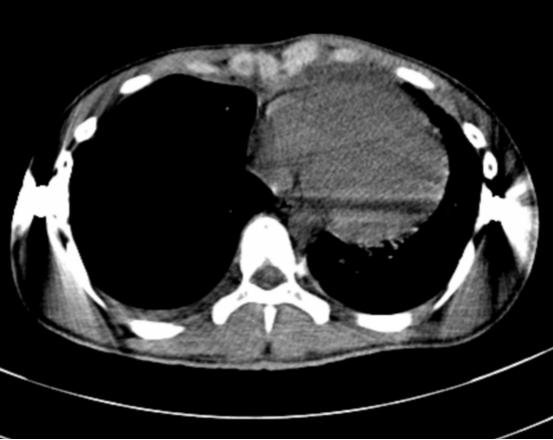

术前术后对比,胸前区凹陷畸形得到明显的改善